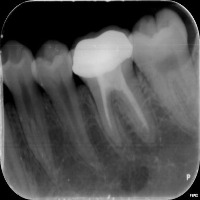

Dental Health Monitoring: This computer vision model can be used by dental professionals and healthcare providers to monitor patients' dental health by evaluating teeth x-rays and identifying specific classes to detect decay, infections, or tooth misalignment.

Dental Education and Training: Dental students and professionals can leverage this model as a learning tool to study and understand different vqc classes, such as P3, P4, and P5, and their implications in various dental conditions and their corresponding required treatments.

Customized Orthodontic Treatment Planning: The model can analyze x-rays to identify individual tooth structure, allowing orthodontists to create customized and more precise treatment plans for improving dental alignment and addressing various occlusion issues.